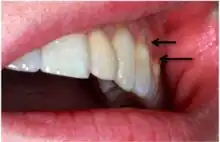

A systematic review by Teixeira et al. reported that most diagnoses of NCCL are derived from a combination of visual and tactile clinical examinations[11] under adequate illumination. This is depicted as a clinical loss of mineralized dental tissue at the cementoenamel junction (CEJ) in the buccal or lingual dental surfaces. There is also a consensus that visual dentine exposure is a reliable indicator of loss of tooth tissue.[14]

Tactile clinical examination involves running an exploratory probe laterally against the cervical surfaces of the tooth at the location of the suspected lesion. The lesion should feel smooth and non-cavitated.